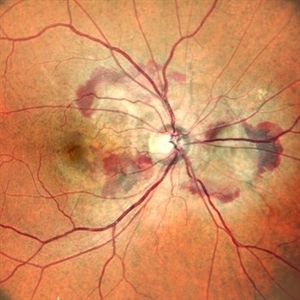

Right Eye Color Photo With Hemorrhages in Case of CNVM With Angioid Streaks

Right Eye Color Photo With Hemorrhages in Case of CNVM With Angioid Streaks

Nov 29 2024 by Anand Temkar

A 45 year old male came with chief complaint of blurring vision in right eyes since past 4 days. His vision is 6/12 in right eye and 6/9 in left eye. His vision was 14 mmHg in right eye and 16 mmHg in left eye. He was diagnosed with Angioid Streaks in both eyes about a year ago, then he developed choroidal neovascularization in his left eye 8 months ago, for which he received AntiVEGF injections x 3. Left eye is a stable eye now. Patient presented with right eye choroidal neovascularization in a case of Angioid Streaks on recent follow up. We have advised him right eye AntiVEGF injections x 3. In this image, the right eye color photo shows bleed from CNVM in case of angioid streaks.

Photographer: Dr.Anand Temkar- Retina Foundation, Ahmedabad

Imaging device: Mirante

Condition/keywords: Angioid Streaks, choroidal neovascular membrane (CNVM)